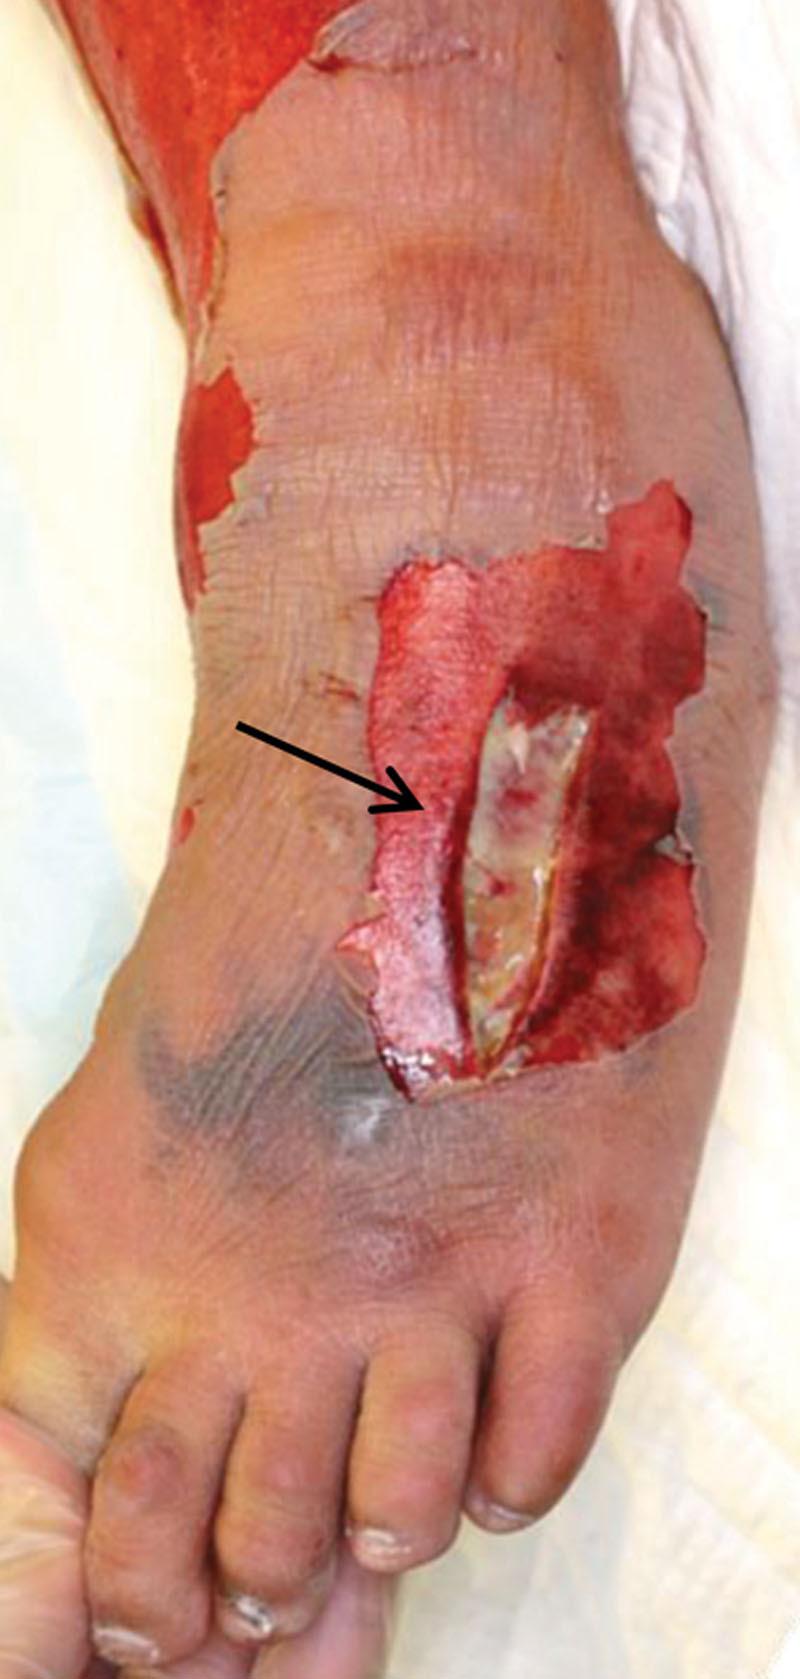

Limitations of a Rapid Antigen Detection Test in the Early Diagnosis of Group A Streptococcal Necrotizing Soft Tissue Infection.

Plast Reconstr Surg Glob Open. 2020 Sep 21;8(9):e3110. doi: 10.1097/GOX.0000000000003110. eCollection 2020 Sep.